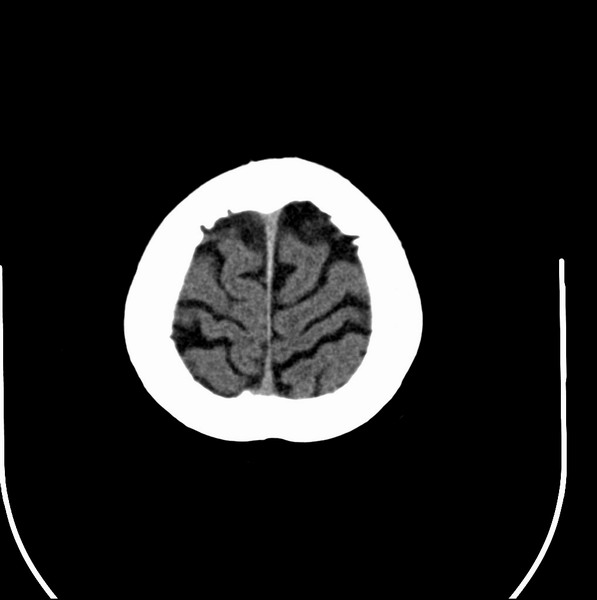

以下是引用余辉在2009-4-25 10:34:00的发言:[br]上矢状窦旁软组织肿块,内有钙化,与上矢状窦边界不清,灶后颅骨内板骨质增生硬化,支持考虑脑膜瘤,建议增强

以下是引用hmyj9在2009-4-25 14:21:00的发言:[br]病灶紧贴颅板处,中心高密度周围见软组织密度,局部颅板有增生,支持脑膜瘤诊断,建议增强。

以下是引用边生丽在2009-4-25 11:55:00的发言:[br][br] [br] 考虑脑膜瘤可能性大;建议行进一步检查。 [br] [br] [br]